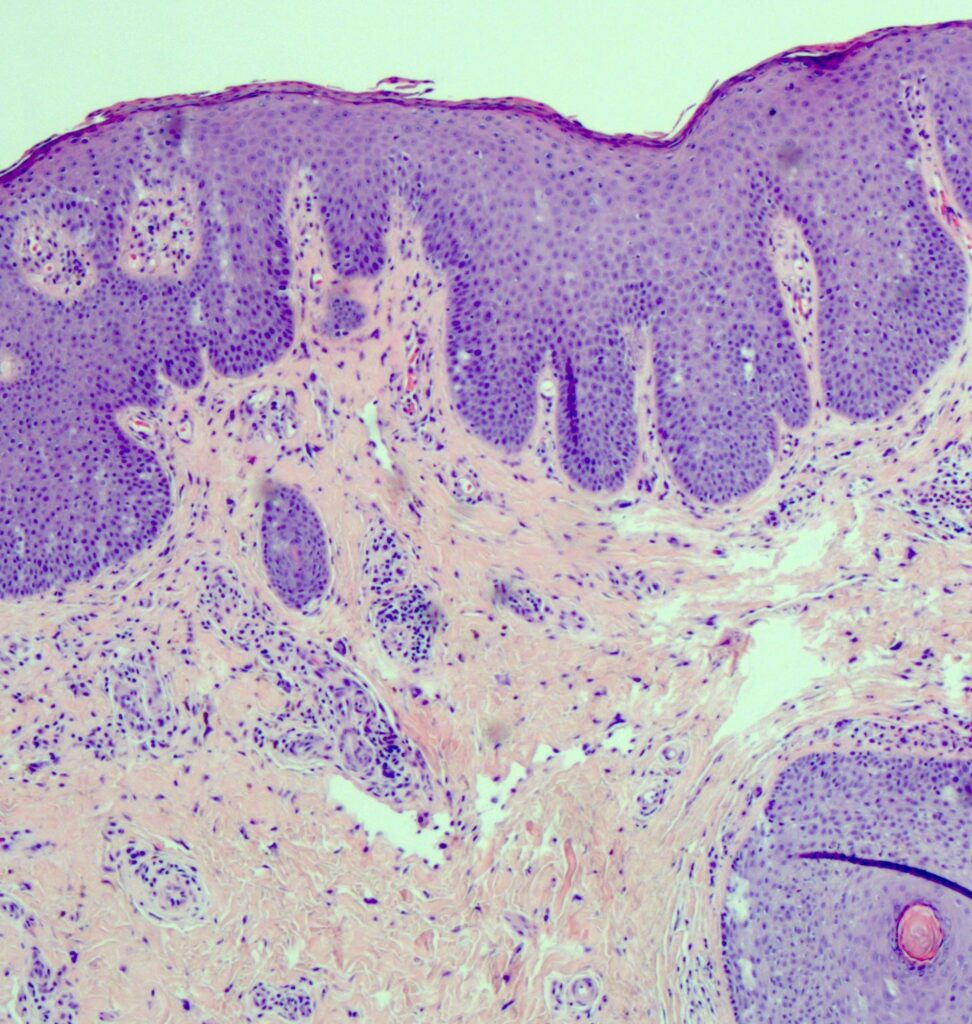

Il termine “Lichen” si riferisce a condizioni infiammatorie o patologiche della pelle, e in ginecologia, ne esistono diverse tipologie.

Ad esempio, il Lichen Sclerosus e il Lichen Planus possono influenzare l’area vulvare, causando prurito, dolore e arrossamento.

Queste sono patologie croniche che richiedono una gestione attenta.

Il Lichen Simplex invece è una forma di dermatite che causa un’intensa sensazione di prurito che, a lungo andare, determina delle alterazioni della pelle, quali secchezza, desquamazione, discromie e vesciche.

I sintomi possono variare, ma comunemente includono secchezza vaginale, prurito, bruciore e dolore durante i rapporti sessuali. Nel caso del Lichen, si possono osservare lesioni, erosioni o ulcere vulvari.

La diagnosi si basa sulla valutazione clinica e, in alcuni casi, potrebbe essere necessaria una biopsia per confermare il tipo di Lichen. È fondamentale comunicare apertamente con il proprio ginecologo per garantire una diagnosi accurata.